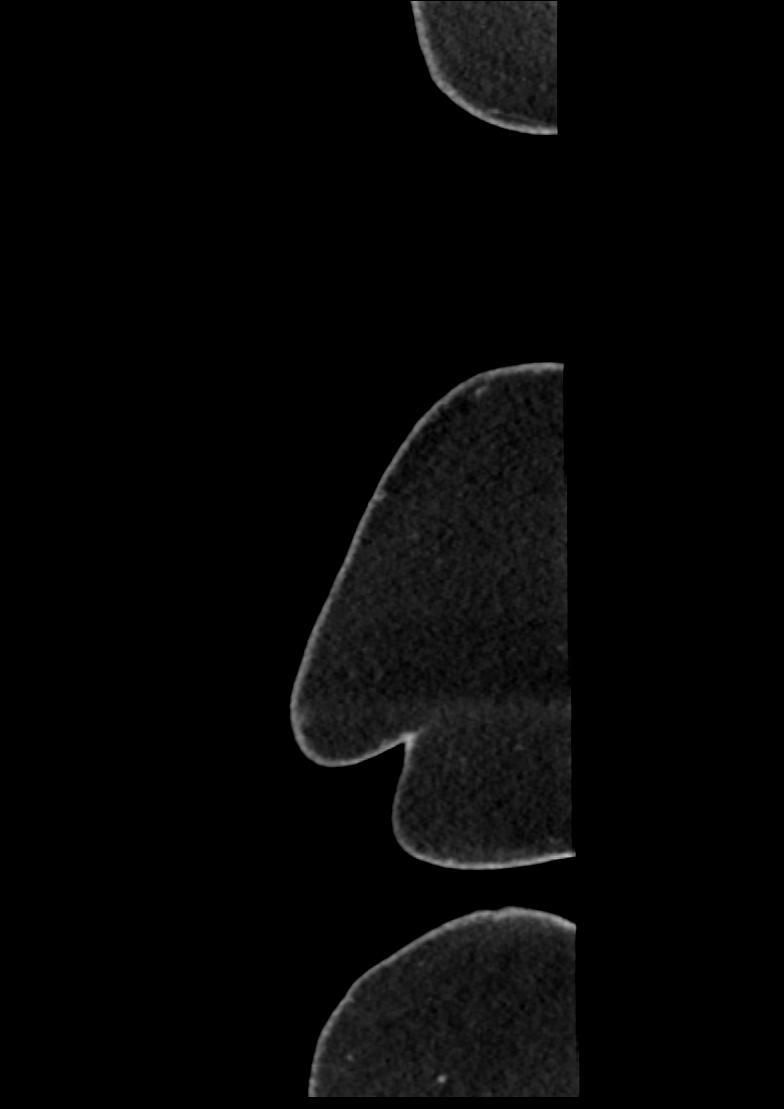

Study Description: CT ABDOMEN

Image Series: Abdomen Sag 3mm [4]

<< Previous | Image 2 of 158 | Next >>